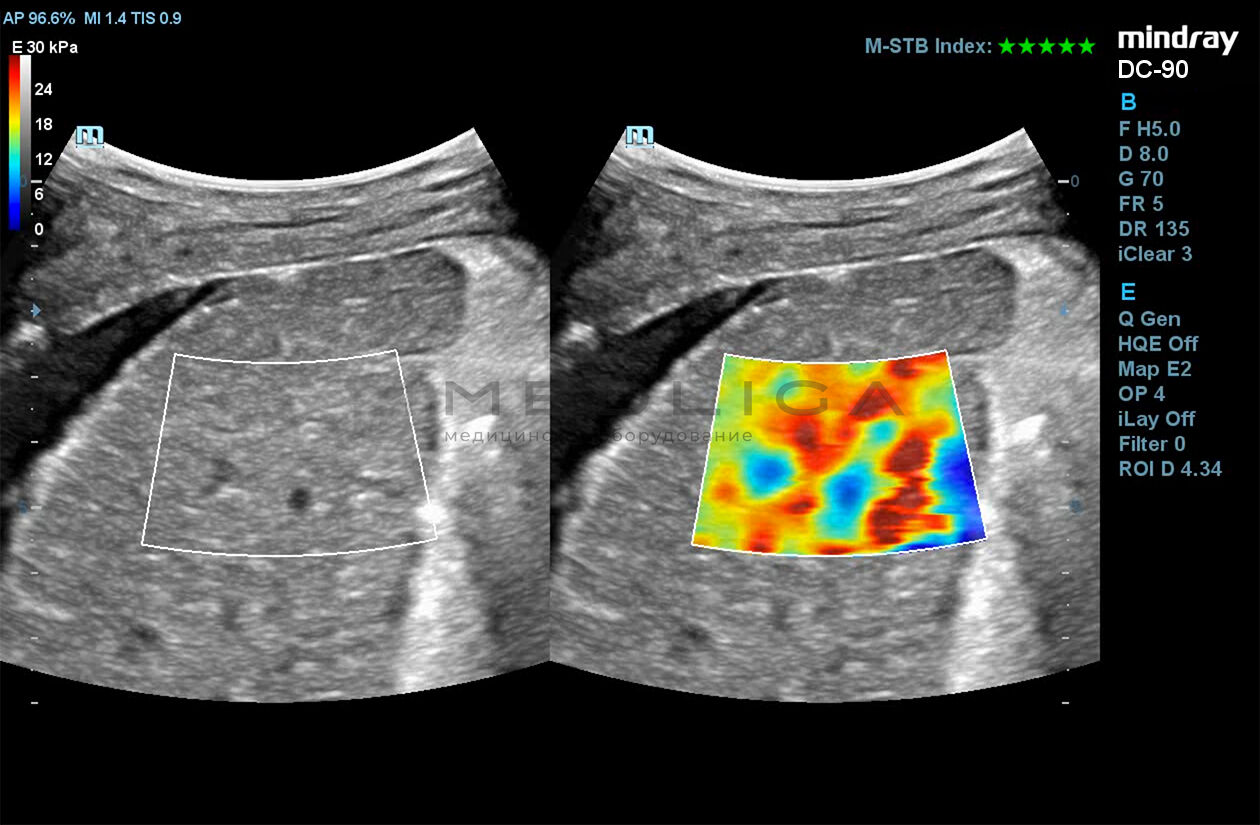

Программное обеспечение для оценки эластичности ткани методом эластографии сдвиговой волны (метод 2D-с формированием двухмерной цветовой эластограммы и количественной оценкой эластичности) на линейных и конвексных датчиках.

STE интегрирована с эксклюзивной технологией Ultra-Wide Beam Tracking от Mindray для двумерной эластографии сдвиговой волной в реальном времени. Специализированные измерительные инструменты позволяют проводить количественный анализ модуля упругости с высокой точностью.

• на линейных датчиках

• на конвексных датчиках